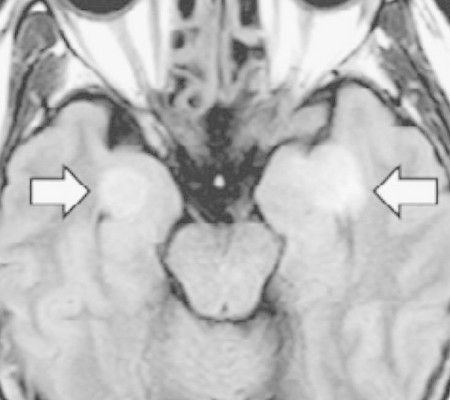

A ciência ainda não desvendou como o coronavírus pode atacar o cérebro. Mas chamou atenção o caso de uma funcionária de uma companhia área nos EUA de 58 anos, sem comorbidades. Com diagnóstico de Covid-19, ela desenvolveu encefalopatia aguda necrotizante, uma doença rara e gravíssima.

Ela teve sintomas como desorientação e perda de memória em apenas três dias. O caso foi descrito na revista médica Radiology. A mulher sobreviveu, mas não se sabe se terá sequelas.

Casos de derrames, convulsões, inflamação cerebral e confusão mental já foram observados em pacientes com Covid-19. Os médicos ainda não sabem se são causados pela ação direta do coronavírus ou pela inflamação associada a ele.